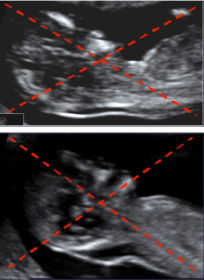

Le grossissement de l’image doit être telle que la tête fœtale et la partie supérieure du thorax occupent l’ensemble de l’écran.

- Une coupe sagittale du fœtus doit être obtenue. Dans cette coupe, l'os propre du nez échogène et le palais rectangulaire sont vus séparément. La rotation de la tête hors de la ligne médiane entraîne la disparition de la pointe du nez et l'apparition de l'os maxillaire comme structure échogène entre l'os nasal au-dessus et la partie antérieure du palais en bas. Avec une rotation supplémentaire de la ligne médiane, l'os propre du nez disparaît et il y a élargissement de l'os maxillaire et fusion avec le palais.

- Le fœtus doit être dans une position neutre, avec la tête alignée par rapport à la colonne vertébrale. Lorsque la nuque du bébé est en hyper-extension, les mesures peuvent être faussement augmentées et quand la nuque est en flexion, les mesures peuvent être faussement diminuées.

- Des précautions doivent être prises pour faire la distinction entre la peau du fœtus et l’amnios